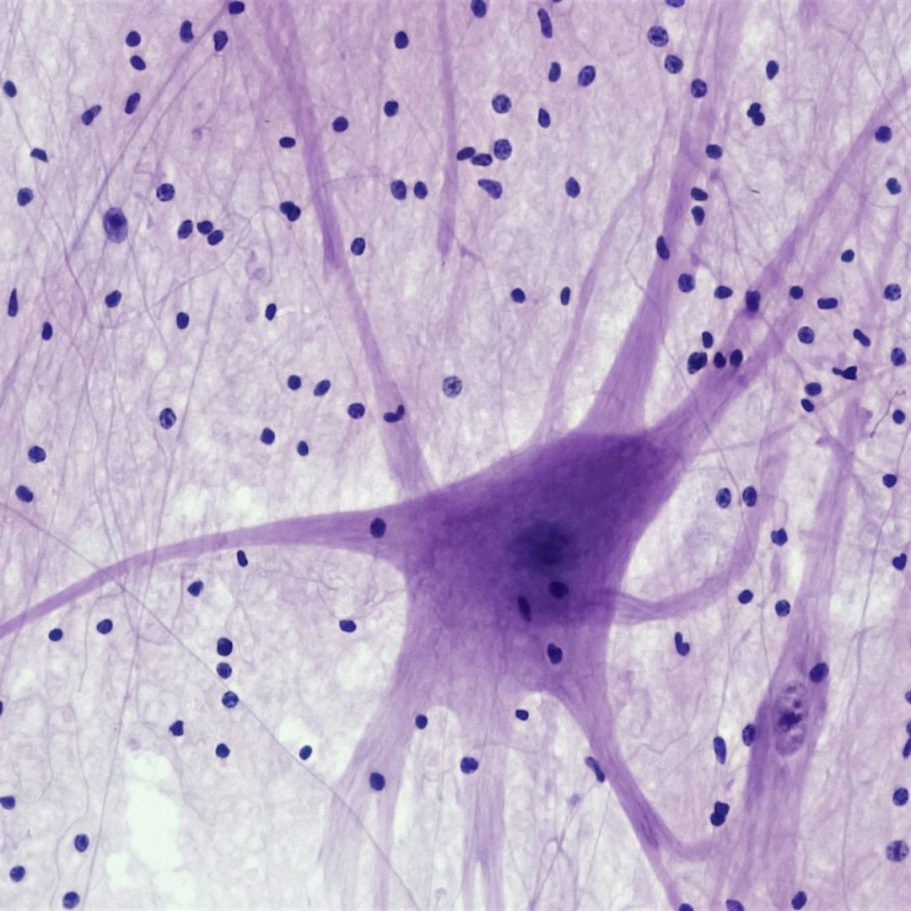

Der osteopathische Ansatz berücksichtigt das enge Zusammenspiel von Bewegungsapparat, Organen und Nervensystem. Störungen in einem dieser Bereiche können sich auf den gesamten Organismus auswirken. Durch sorgfältige Untersuchung und sanfte, manuelle Techniken lassen sich Spannungen, Blockaden und Funktionsstörungen aufspüren und behandeln.

Nerven und Koordination

Harmonisierung von Nervensystem und Körperfunktionen zur Verbesserung von Koordination, Reaktionsvermögen und innerer Balance.